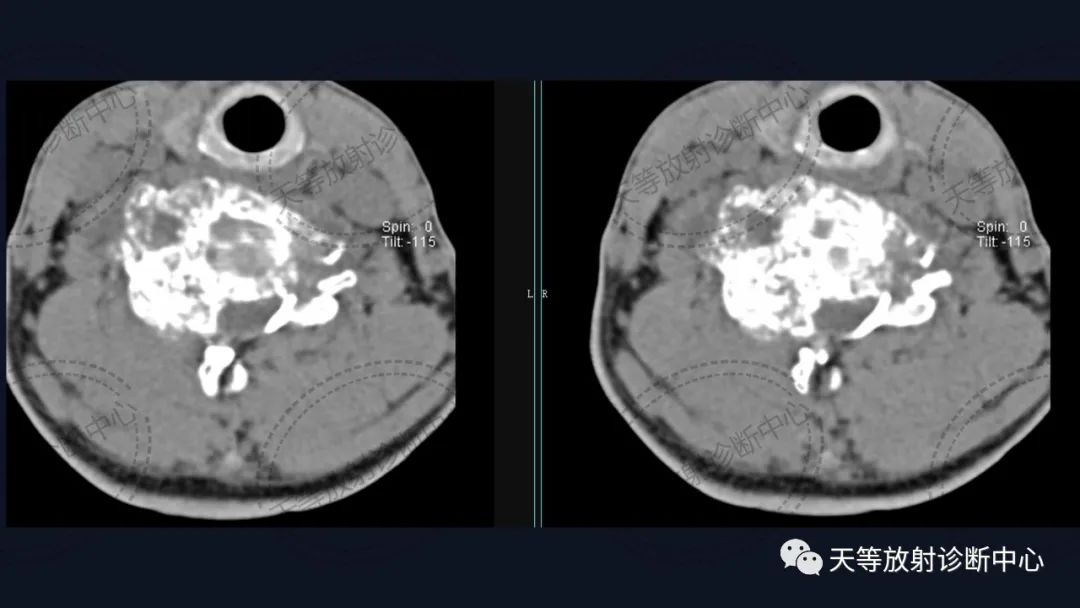

术后内固定支架

肿瘤复发,椎旁分叶状软组织肿块,内部信号不均,混杂信号,高低信号不等,内见线状小叶间隔。

DWI信号较高,内部钙化灶呈散在泥沙样低信号灶。

诊断软骨肉瘤复发。